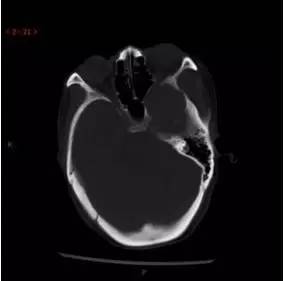

CT平扫轴位

解析:本病例为中颅窝至颞下窝沟通性病变,对周围骨质主要呈膨胀压迫性改变,伴囊变、出血。